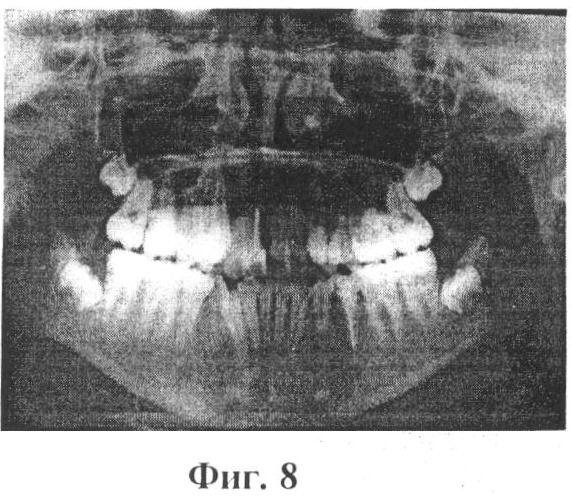

Изобретение иллюстрируется фотографиями, где на фиг.1 и 2 показаны зубные ряды верхней и нижней челюстей пациентки А., на фиг.3 – расположение несъемного аппарата с тремя направляющими на верхней челюсти для расширения и удлинения верхнего зубного ряда (стрелками указано направление активации винта), на фиг.4 показана реплантация клыка и премоляра, фиксация брекетов на эти зубы, шинирование в зубном ряду при помощи ортодонтической дуги и металлических лигатур, разобщение прикуса за счет окклюзионных накладок из стеклоиономерного цемента на 36 и 46 зубы, на фиг.5 показаны фотографии зубных рядов пациентки А. после ортодонтического лечения, на фиг.6 показана фиксация брекетов, колец и небного бюгеля на зубы верхней челюсти, на фиг.7 – зубные ряды пациентки А. верхней и нижней челюстей после ортодонтического лечения, на фиг.8 – ортопантомограмма пациентки А. до ортодонтического лечения, на фиг.9 – ортопантомограмма пациентки А. через 6 месяцев после реплантации клыка и премоляра, на фиг.10 – ортопантомограмма пациентки А. после ортодонтического лечения, на фиг.11 – телерентгенограммы пациентки А. до и после ортодонтического лечения, на фиг.12 и 13 – гипсовые модели пациентки А. до и после ортодонтического лечения соответственно.

На основе клинических и дополнительных методов исследования был поставлен диагноз: нейтроокклюзия, сужение и укорочение верхнего зубного ряда, вестибулярное положение 13, 23, 43 зубов; дефицит места в зубном ряду; адентия 44, транспозиция 33 (на месте 44), разворот по оси на 180°; небное положение 12, 22 зубов; тесное положение резцов на верхней и нижней челюсти I и II степени.

После окончания активного ортодонтического лечения профиль и улыбка пациентки А. (14 лет 6 мес.) значительно улучшились (фиг.7). На верхнюю челюсть был изготовлен съемный ретейнер и несъемный на зубы нижней челюсти (фиг.8). Реплантированные зубы болезненных ощущений у пациентки А. не вызывали на протяжении всего курса ортодонтического лечения. При осмотре полости рта подвижности этих зубов не наблюдалось. Электроодонтодиагностика клыка после снятия брекетов была равна 13 мкА, премоляра – 19 мкА.

Нестандартность проведенного комплексного лечения состояла в применении брекет-системы и несъемного аппарата с тремя направляющими (винт Бертони) для расширения и удлинения верхнего зубного ряда и реплантации клыка и премоляра с использованием синтетического коллаген-апатитового материала «ЛитАр» для оптимизации репаративного остеогенеза. У данной пациентки проведена компьютерная томография верхней и нижней челюсти, ортопантомография и телерентгенография, изучение гипсовых моделей челюстей до и после ортодонтического лечения (фиг. 9, 10, 11, 12, 13, 14).